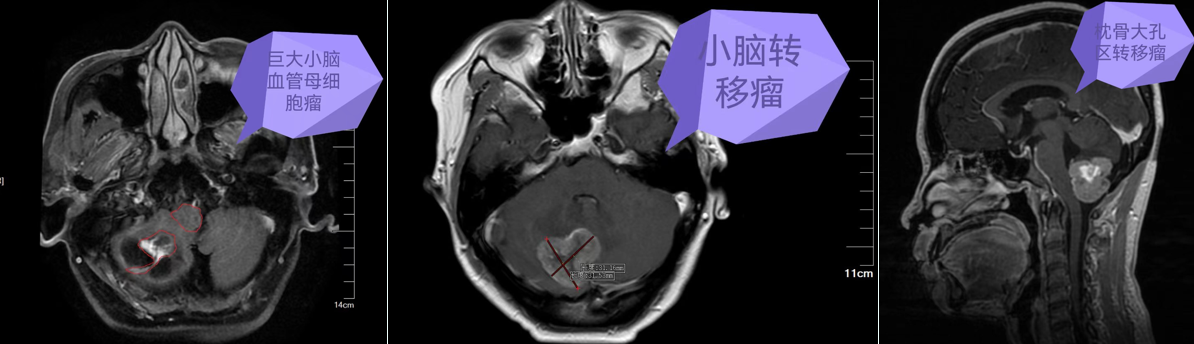

图片 3.png

Ommaya泵侧脑室置入术肿瘤颅内多发转移瘤

图片 5.png

神经导航引导下大脑半球巨大占位微创切除术

图片 6.png

神经导航引导下小脑半球巨大占位微创切除术

图片 7.png

挑战生命禁区,颅底、侧颅底占位微创切除术

从Ommaya囊侧脑室置入术到大脑半球、小脑半球占位切除术,从垂体瘤到颅底、侧颅底等复杂颅内占位切除术,凭借先进的微创技术与高精尖的设备,为众多患者解除了病痛,让患者重新找回了生活的精彩。